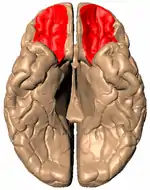

El giro orbital, destacado en rojo.

La corteza orbitofrontal (COF) es la región del lóbulo frontal del cerebro relacionada con el procesamiento cognitivo de la toma de decisiones. En primates no humanos, incluye las áreas corticales de asociación de Brodmann 11, 12 y 13. En los seres humanos, comprende las áreas 10, 11 y 47 de Brodmann.[1] Dado que ha sido relacionada con los mecanismos de procesamiento de la emoción y de la recompensa, algunos autores consideran que la COF forma parte del sistema límbico.

Anatómicamente, la COF se define como la parte de la corteza prefrontal que recibe proyecciones desde los núcleos mediales magnocelulares del tálamo mediodorsal.[2] Su nombre se debe a su posición, ya que se encuentra situada inmediatamente sobre las órbitas en las que se ubican los ojos. Se ha hallado una considerable variabilidad individual en la COF, tanto en primates humanos como en no humanos. En los roedores se ha encontrado un área similar.[3]